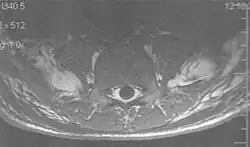

Metal artifacts

Metal artifacts occur at interfaces of tissues with different magnetic susceptibilities, which cause local magnetic fields to distort the external magnetic field. This distortion changes the precession frequency in the tissue leading to spatial mismapping of information. The degree of distortion depends on the type of metal (stainless steel having a greater distorting effect than titanium alloy), the type of interface (most striking effect at soft tissue-metal interfaces), pulse sequence and imaging parameters. Metal artifacts are caused by external ferromagnetics such as cobalt containing make-up, internal ferromagnetics such as surgical clips, spinal hardware and other orthopaedic devices, and in some cases, metallic objects swallowed by people with pica.[3] Manifestation of these artifacts is variable, including total signal loss, peripheral high signal and image distortion (Figs 3 and 4).[1] Reduction of these artifacts can be attempted by orientating the long axis of an implant or device parallel to the long axis of the external magnetic field, possible with mobile extremity imaging and an open magnet. Further methods used are choosing the appropriate frequency encoding direction, since metal artifacts are most pronounced in this direction, using smaller voxel sizes, fast imaging sequences, increased readout bandwidth and avoiding gradient-echo imaging when metal is present. A technique called MARS (metal artifact reduction sequence) applies an additional gradient, along the slice select gradient at the time the frequency encoding gradient is applied.